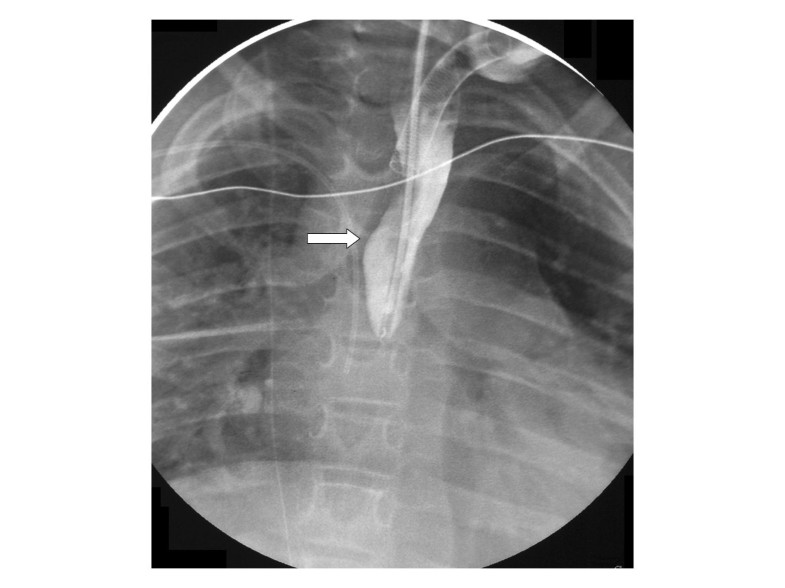

Patient 2. Esophagogram depicting a leftsided leak. Download Scientific Diagram Esophagostomy Tube Complications Any medical procedure can result in unexpected complications. mechanical complications include both tube obstruction and premature removal of the tube or dislodgement from. One hundred patients (44.4%) experienced a complication related to tube placement, with a similar complication rate among dogs (43.1%). esophagostomy tubes can stay in place for months without needing to be replaced. for those. Esophagostomy Tube Complications.